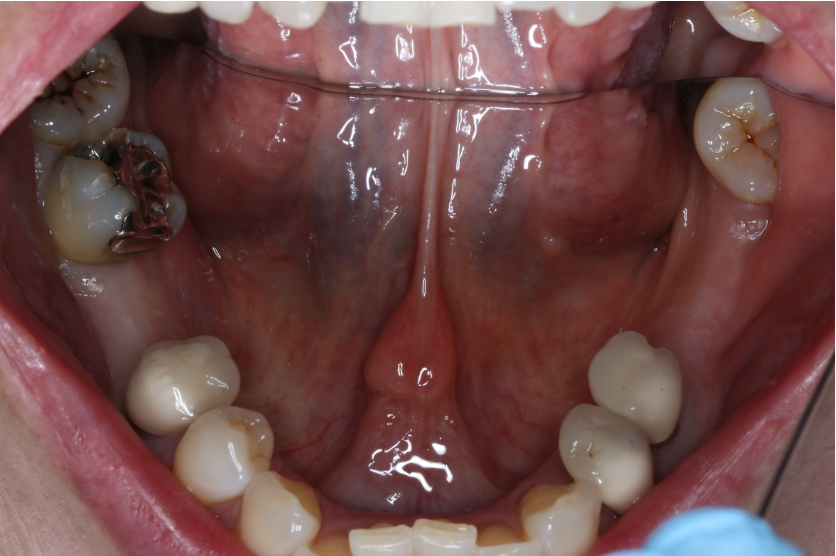

セラミック症例①

年齢40代女性

治療期間1ヶ月

治療内容ジルコニア、セラミックインレー、セラミッククラウン

治療箇所左上1番、2番 左下5番、7番 右上1番、2番、3番、4番、5番 右下5番、6番、7番

治療費用100,000円